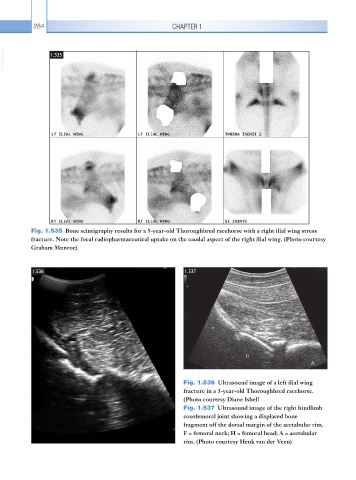

Fig. 1.535 Bone scintigraphy results for a 5-year-old Thoroughbred racehorse with a right ilial wing stress

fracture. Note the focal radiopharmaceutical uptake on the caudal aspect of the right ilial wing. (Photo courtesy

Graham Munroe)

Fig. 1.536 Ultrasound image of a left ilial wing

fracture in a 3-year-old Thoroughbred racehorse.

(Photo courtesy Diane Isbell

Fig. 1.537 Ultrasound image of the right hindlimb

coxofemoral joint showing a displaced bone

fragment off the dorsal margin of the acetabular rim.

F = femoral neck; H = femoral head; A = acetabular

rim. (Photo courtesy Henk van der Veen)